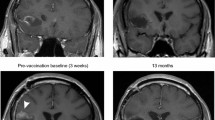

In patient #5, a sudden onset right hemiplegia and aphasia occurred at 8 months FU (after the third boost with tumor lysate). MRI showed hyperintensities in T2 weighted images and heterogenic signals in T1 weighted images at the posteromedial side of the left temporal lobe, near the site of tumor resection (Fig. 3a, b). These MRI data were most compatible with ischemic changes and the episode of hemiplegia and aphasia was diagnosed as an ischemic event. Inflammation, in terms of auto-immunity, could not be ruled out as no biopsy was performed. A repeat MRI three months after the described event showed the same changes at the posteromedial side of the left temporal lobe without any evolution (Fig. 3c–e). We concluded that these changes were most likely to be ischemic, although inflammation or post-radiotherapy sequellae could not be ruled out pathologically in this young patient; the clinical evolution was favorable without administration of steroids. In the same patient the TMZm chemotherapy was stopped because of hematological toxicity (grade 3) and at one year FU this same patient had a status epilepticus which was controlled with fenytoin. Tumor status at that time remained unchanged. No other serious adverse events have been reported.

Patient #5: MRI images at eight and eleven months follow-up (FU). Hyperintensities in T2 weighted images (a) and heterogenic signals in T1 weighted images (b) at the posteromedial side of the left temporal lobe, near the site of tumor resection, one day after sudden onset of right hemiplegia and aphasia (at eight months FU). A repeat MRI three months after the described event shows the same changes at the posteromedial side of the left temporal lobe without any evolution; c T2 weighted images; d T1 weighted images; e T1 weighted images with gadolinium